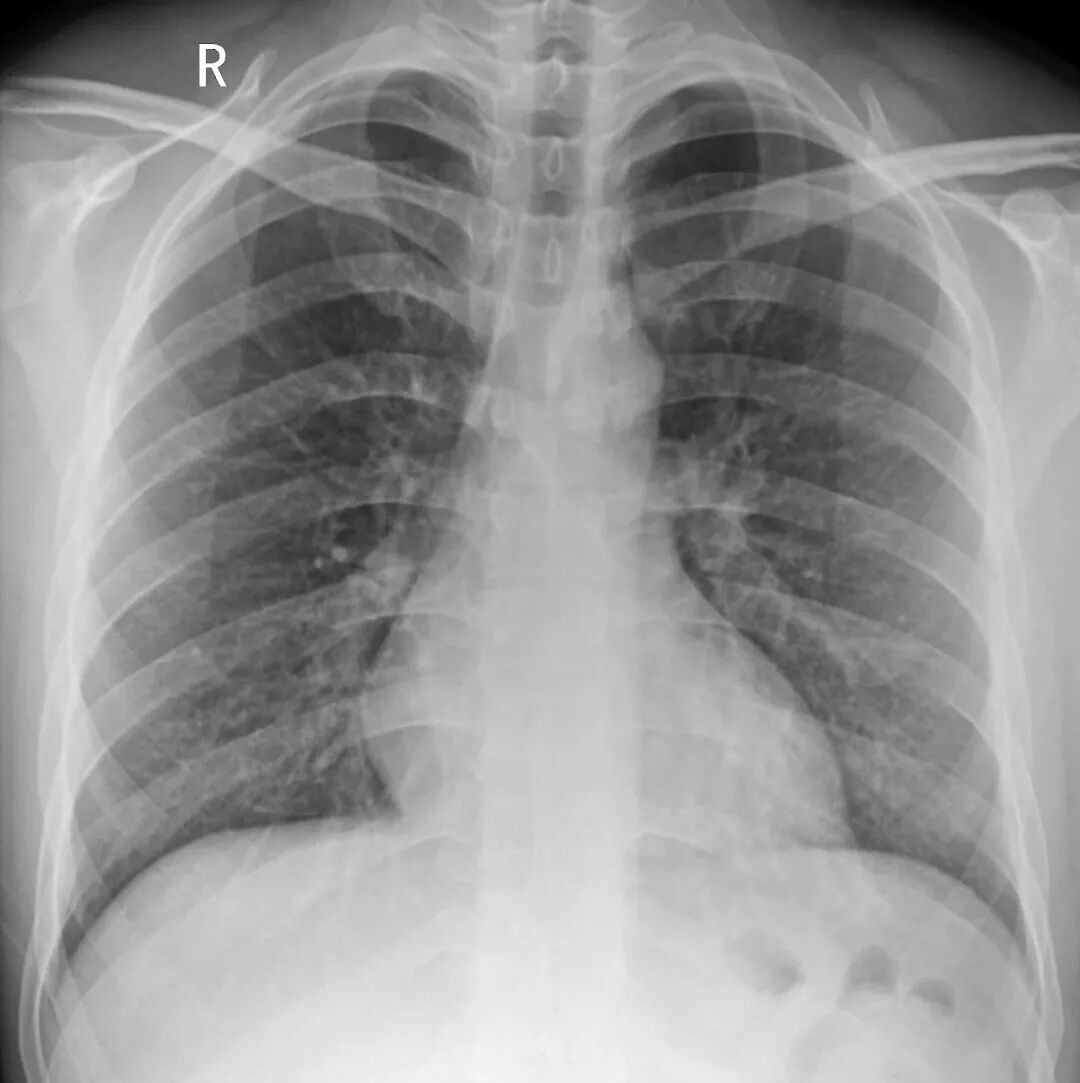

胸透和胸片主要用于检查诊断肺部疾病、心脏的大小、肋骨、胸膜、胸壁纵隔、支气管。为减少X线的损害,患者做检查不宜过多。

胸片DR和胸透还是有很大的区别的,当然它们都是检查胸部,也就是看肺这一块的。但是它们的区别还是比较大的,首先第一点它的辐射剂量有很大的差别,胸片DR,它的辐射剂量是非常的小,而胸透相对来说就要大一些了,主要是跟它辐射的时间有关系。

做胸片DR检查的话,它辐射的时间是非常短的,一般也就是零点零几秒的时间,非常的短,而胸透检查它这个辐射时间相对来说就要长一些了,一般是需要十秒钟的时间。当然如果发现有可疑的病灶,可能需要看的时间要更长一些了。正因为是这样,所以现在很多医院已经基本上取消了胸透检查了,都是用胸片来进行替代。

胸片的话一般是可以照出一张片子来,而胸透只是医生通过目视,通过眼睛来看,看完之后得出一个纸质报告,是没有这种片子的。

胸部 肺、胸膜及纵膈各种肿瘤、肺结核、肺炎、支气管扩张、肺脓肿、囊肿、肺不张、气胸、骨折等;对于显示肺部病变有非常满意的效果,对肺部创伤、感染性病变、肿瘤等均匀有很高的诊断价值。对于纵隔内的肿物、淋巴结以及胸膜病变等的显示非常清晰也令人满意,可以显示肺内团块与纵隔关系等。

最常用X光片、CT大致了解选X光片,细致分析选CT肺的检查一般不选核磁

胸部